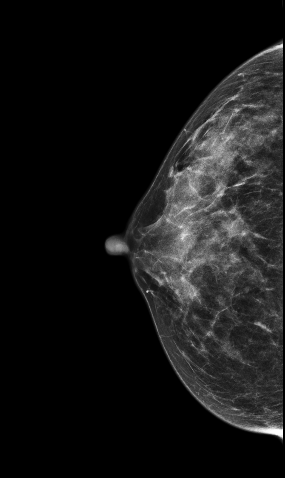

V-preview图像:

影像描述: 在2DMLO位图像的上象限发现一不对称局限性致密影,但CC位上未见明显异常病变区域,在V-Preview图像上MLO位上病变显示明显逼2D更清晰,在CC位上乳头后方深部我们可以清晰的发现病灶,在3D-plane图像上我们可以更进一步清楚观察到病变形态大小范围,以及病灶边缘呈星芒样长短不一毛刺样改变。 影像诊断: 右乳偏外象限局限致密影,考虑BI-RADS 4B 。 病例点评: 病理证实右乳浸润性导管癌,DBT可以给我们提供更多诊断信息有助于明确病变性质。